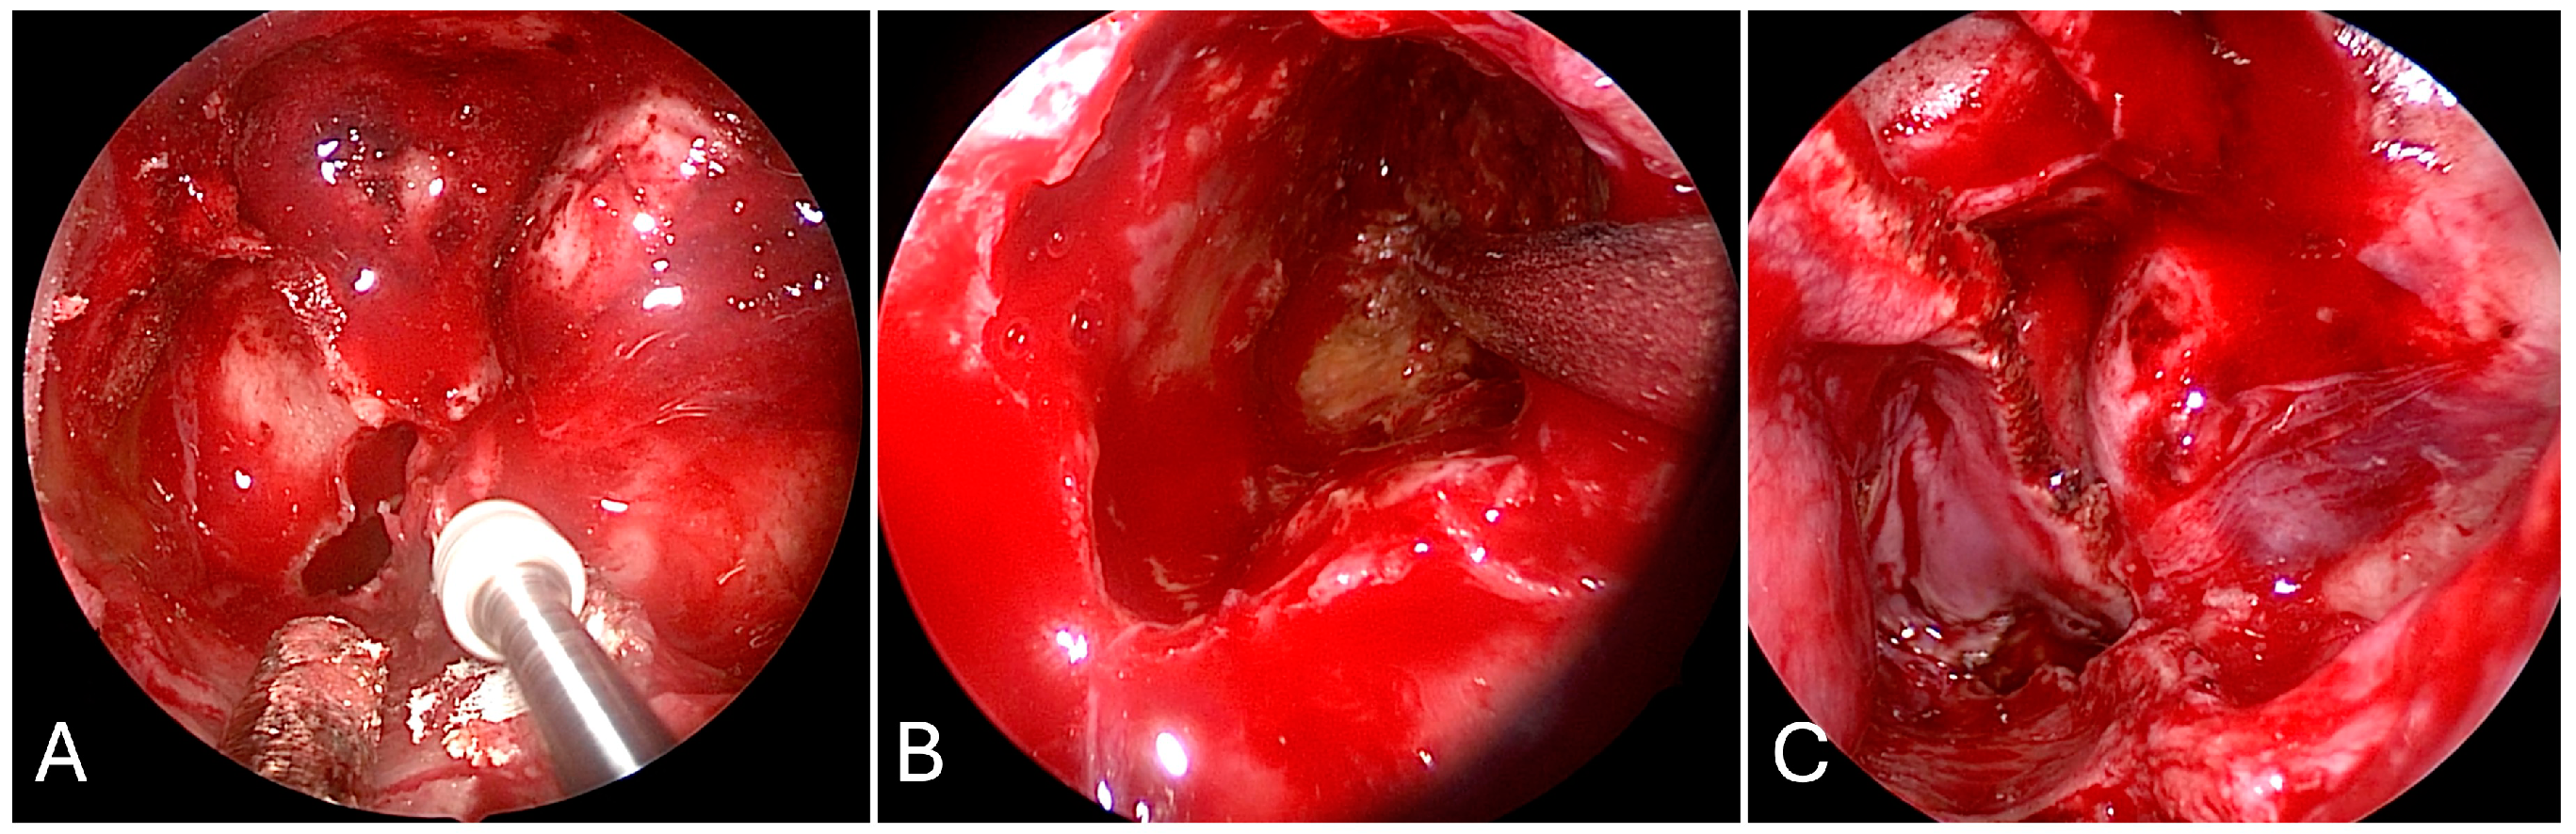

3.4.2. Illustrative Case

3.4.3. Practical Pearls

- Sacrifice of the sphenopalatine artery in the transpterygoid approach precludes an ipsilateral nasoseptal flap.

- Skeletonization of the maxillary nerve leads to the ‘quadrangular space’ and Meckel’s cave.

- Skeletonization of the vidian nerve leads to the lacerum segment of the ICA.

- The contralateral transmaxillary approach may be a useful back up option for lateral petrous pathologies approaching the IAC.